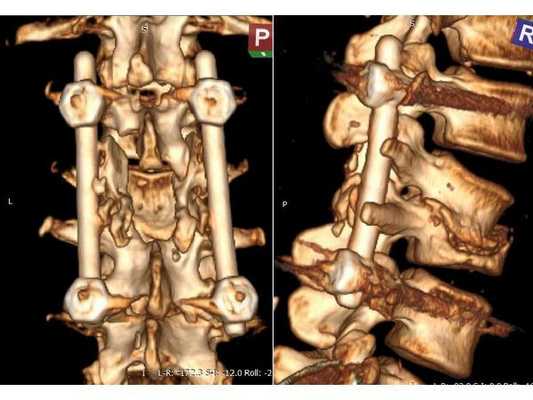

Пациентке проведена операция: транспедикулярная фиксация позвоночника L1-L4 и ламинэктомия L2 (удаление дужки позвонка с целью декомпрессии). Ход операции: • При положении пациентки лёжа на животе в проекции остистых отростков L1-L4 произведён прямой вертикальный разрез мягких тканей размером 10 см. • Надкостницы поперечных отростков и дугоотросчатых суставов отделены от костей. Кровотечение остановлено при помощи электрокоагуляции по ходу доступа. • Под контролем рентгена выявлены ножки L1 и L4 позвонков и сформированы каналы в тела самих позвонков, через которые в их ножки введены моноаксиальные педикулярные винты. • Проведена ламинэктомия позвонка L2. При ревизии твёрдой мозговой оболочки, окружающей спинно-мозговые корешки, на уровне L2-L3 позвонков обнаружены выраженные изменения рубцово-спаечного характера. • Рана промыта при помощи физраствора и раствора перекиси водорода. Поверх твёрдой мозговой оболочки уложена гемостатическая губка. Установлены две продольные штанги, закручены стопорные гайки. • В конце на рану наложен послойный шов нитью Викрил и асептическая повязка.

После операции в неврологическом статусе наблюдается положительная динамика: умеренный парапарез в нижних конечностях почти полностью регрессировал, жалобы на "онемения в ногах" также исчезли. На контрольной КТ видно состояние после успешной декомпрессии на уровне L2-L3 и установки транспедикулярной фиксирующей системы на уровне L1-L4.